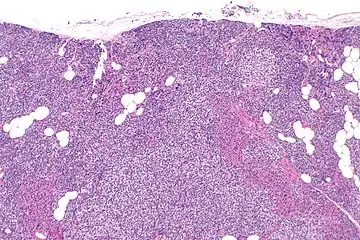

Parathyroid hyperplasia low mag.

Primary hyperplasia of the parathyroid gland, results from both hypocalcaemia and increased phosphate levels by decreasing expression of calcium sensing receptors and vitamin D receptors at the parathyroid gland.[8][4] These decreases in receptor expression lead to hyperfunctioning of the parathyroid. Hyperfunction of the parathyroid gland is thought to exacerbate primary hyperplasia which evolves further to a secondary more aggressive hyperplasia. Histologically, these hyperplasic glands can be either diffuse or nodular.[24] Primary hyperplasia, usually resulting in diffuse polyclonal growth is manly related to reversible secondary hyperparathyroidism. Secondary hyperplasia of the parathyroid gland is more often a nodular, monoclonal growth that sustains secondary hyperparathyroidism and is the catalyst in the progression to tertiary hyperparathyroidism. Nodular hyperplastic glands in tertiary hyperparathyroidism are distinctly larger in both absolute size and weight up to 20-40-fold increases have been reported.[25][26][24]

Parathyroid glands are normally composed of chief cells, adipocytes and scattered oxyphil cells.[27][14] Chief cells are thought to be responsible for the production, storage and secretion of parathyroid hormone. These cells appear light and dark with a prominent Golgi body and endoplasmic reticulum. In electron micrographs, secretory vesicles can be seen in and around the Golgi and at the cell membrane. These cells also contain prominent cytoplasmic adipose.[27][14] Upon onset of hyperplasia these cells are described as having a nodular pattern with enlargement of protein synthesis machinery such as the endoplasmic reticulum and Golgi. Increased secretory vesicles are seen and decreased intercellular fat is characteristic.[27][24] Oxyphil cells also appear hyperplasic however, these cells are much less prominent.